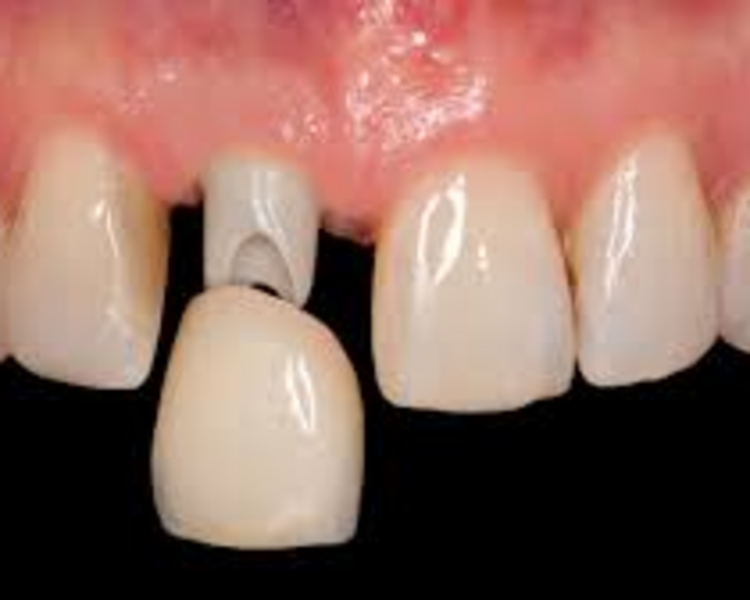

Consiste en la reposición de unidades dentales perdidas por medio de la colocación de implante dental de titanio insertados en los maxilares, a manera de raíces de dientes colocadas dentro del hueso y que luego pueden portar coronas dentales artificiales diseñada para ello. Esta técnica quirúrgica, requiere de estudio, planificación y ejecución cuidadosa soporte.